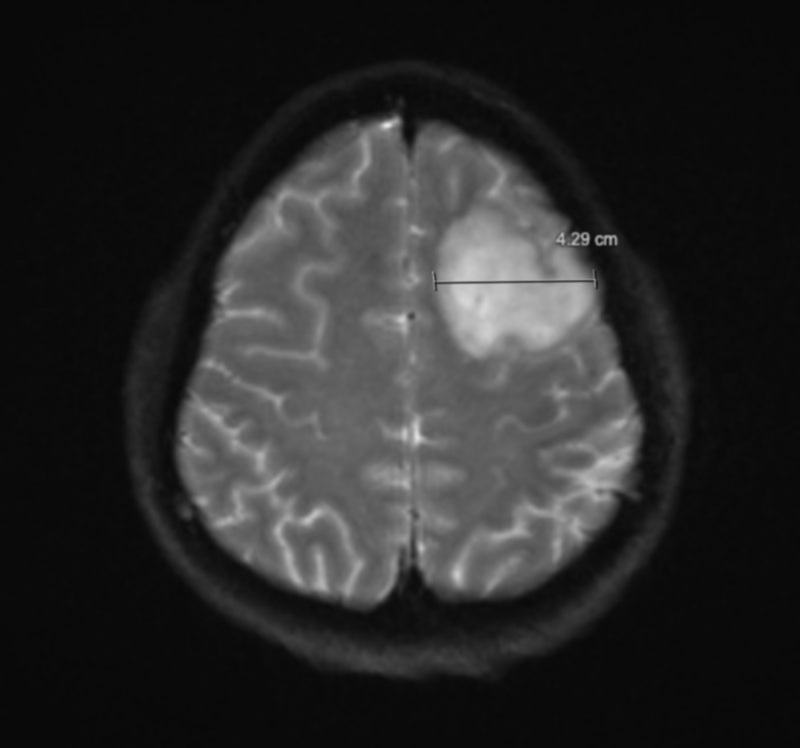

참고로 현재 내가 거주하고 있는 온타리오주 의료보험인 Ontario Health Insurance(OHIP)은 내가 병원에서 검사한 모든 비용을 보장해 줬다. 캐나다 의료 시스템은 악명 높기로 유명한데 이때 정말 위독한 사람에겐 다양한 혜택이 있는 시스템인 것을 처음으로 몸소 느꼈다. 피검사, CT, MRI까지 실험용 쥐 마냥 여기저기 끌려 다니며 정신없이 다음 날이 됐고 의사 선생님이 조심스럽게 부르더니 뇌에 종양이 발견됐다며 내 MRI 사진을 보여줬다. 그렇게 난 만 30살이 되던 해에 뇌종양을 진단받았다.

종양은 좌측 전두엽에 4.29cm로 크게 자라 있었고 우측 측두엽에 작게 위치하고 있었다. 측두엽에 자리 잡은 종양은 내 눈에는 보이지 않을 정도로 작았다. 의사 선생님은 수술을 해야 한다고 했고 머리를 열어야 하는 ‘개두술’을 진행해야 할 것이라고 했다. 전두엽, 측두엽 모두 뇌의 깊은 깊숙한 곳이 아닌 표면에 자리 잡고 있어서 수술 자체는 어려운 편은 아니라고 했다. 이틀간 응급실 복도 생활을 하며 뇌종양이 발견되자 나는 추가 검사를 받기 위해 병실을 배정받았다. 3인실을 사용했는데 나를 제외한 두 분은 백인 할아버지가 사용 중이셨다. 이때 당시에는 코로나로 인해 면회 금지였으며 나는 하루빨리 일상으로 돌아가기만을 고대했다. 사실 이때만 해도 내 상황이 크게 와닿지도 않고 수술 빨리 끝내고 회복해서 결혼식이나 빨리 올리고 싶었다.

좌우 반전 된 나의 뇌 MRI